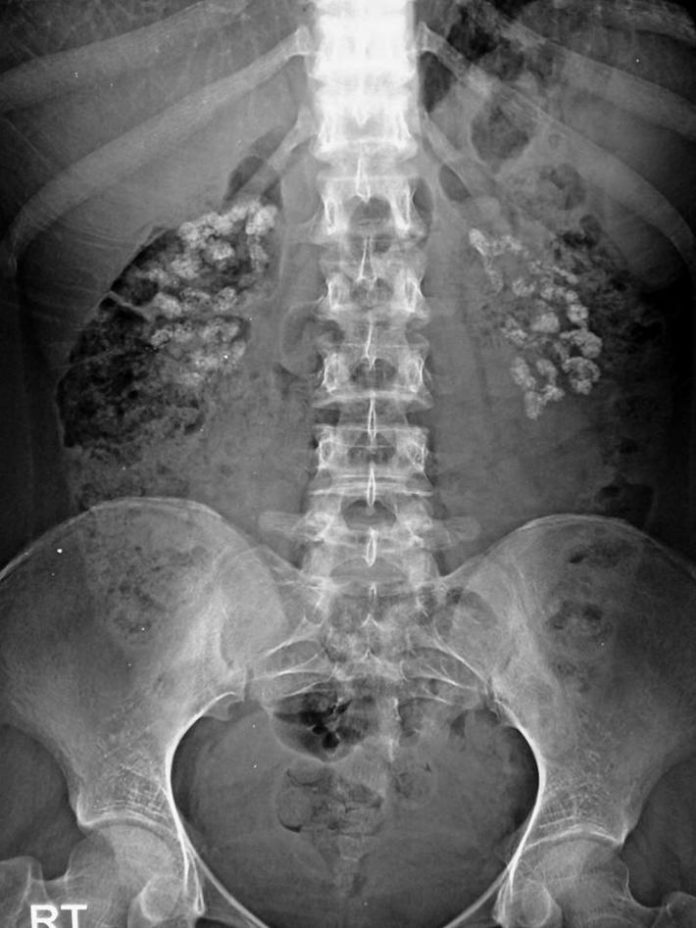

Medullary Sponge Kidney With Nephrocalcinosis . Medullary nephrocalcinosis is defined as the deposition of calcium salts. Medullary sponge kidney is a sporadic condition where the medullary and papillary portions of the collecting ducts are. Nephrocalcinosis may cause acute or chronic kidney injury or be incidentally detected radiographically in a patient with normal kidney. Medullary sponge kidney (msk) is a congenital disorder resulting in ectatic collecting ducts within one or both kidneys. This condition is a disorder with dilated papillary collecting ducts, and stones are common. May present with flank pain, recurrent urinary tract infections (utis), haematuria (gross and microscopic), nephrolithiasis, and. It is associated with hypercalciuria and. Medullary sponge kidney is one of several common causes of medullary nephrocalcinosis.